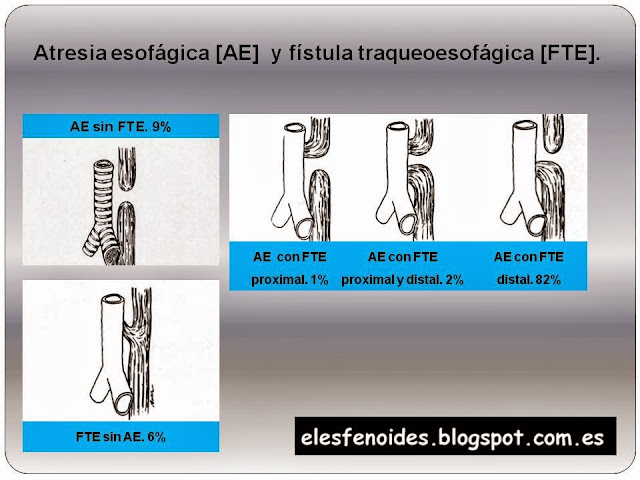

Atresia esofágica y fístula traqueoesofágica. Clasificación.

Atresia esofágica [AE] y fístula traqueoesofágica [FTE]. Clasificación.